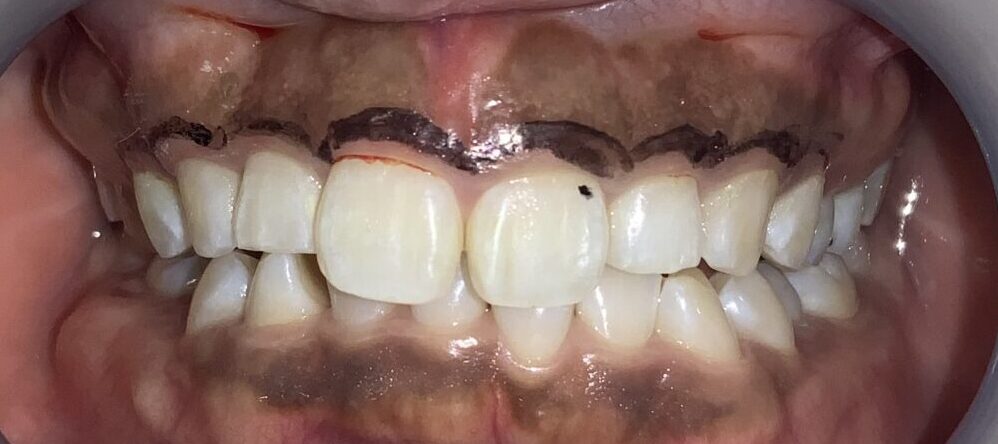

反対側の歯も調べてみます。前歯の形はとても大切ですから、慎重に検査を進めます。

この歯も同じように、たくさんの歯ぐきが、かぶさっています。

隣の歯も同じように検査します。

隣の歯は前歯ほどではないですが、しっかりと歯ぐきが、かぶっています。

この歯は犬歯です。犬歯もたくさんの歯ぐきに覆われているようですが、治療をする場合には注意が必要です。

犬歯はあまり大きくすると、八重歯のように見えてしまい、せっかくの治療が台無しになる場合があります。また、被っている歯ぐきがたくさんあっても、歯ぐきが薄い場合があり、このような歯ぐきの場合は、治療後に歯ぐきが退縮してしまい、歯槽膿漏の歯ぐきのように見えてしまう場合があります。